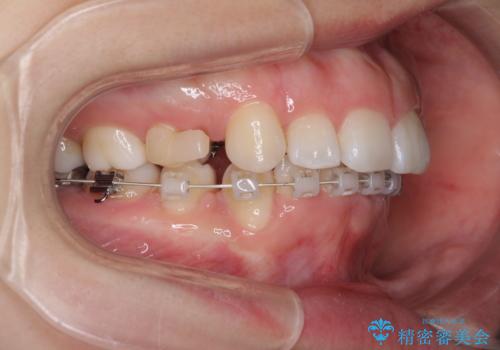

- ハーフリンガル

治療期間の目安は2年半~3年間でしたが、咬み合わせにより上顎装置が頻繁に脱落してしまい、治療期間が長期化してしまいました。